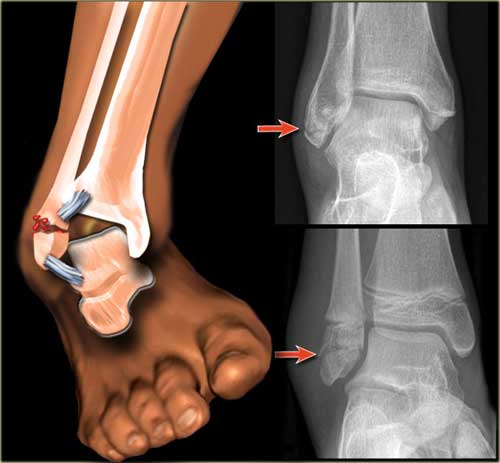

В медицинской практике различают перелом внутренней и наружной лодыжки.

В зависимости от локализации повреждения медики выделяют:

- перелом медиальной лодыжки;

- перелом латеральной.

Перелом наружной лодыжки влечет за собой повреждение малоберцовой кости, в результате которого симптомы травмы могут ощущаться не в полной мере. Объясняется это тем, что эта кость не берет на себя большие нагрузки и крепится к большеберцовой. Наиболее яркий признак в таких случаях – отек голеностопа.

Перелом внутренней лодыжки влечет за собой и нарушение целостности большеберцовой кости. При этом травматологи выделяют:

Бывают случаи, когда нарушается целостность внутренней и наружной лодыжек. Тогда диагностируется краевой перелом – одна из самых тяжелых травм, которая требует длительного лечения и длительного периода реабилитации.